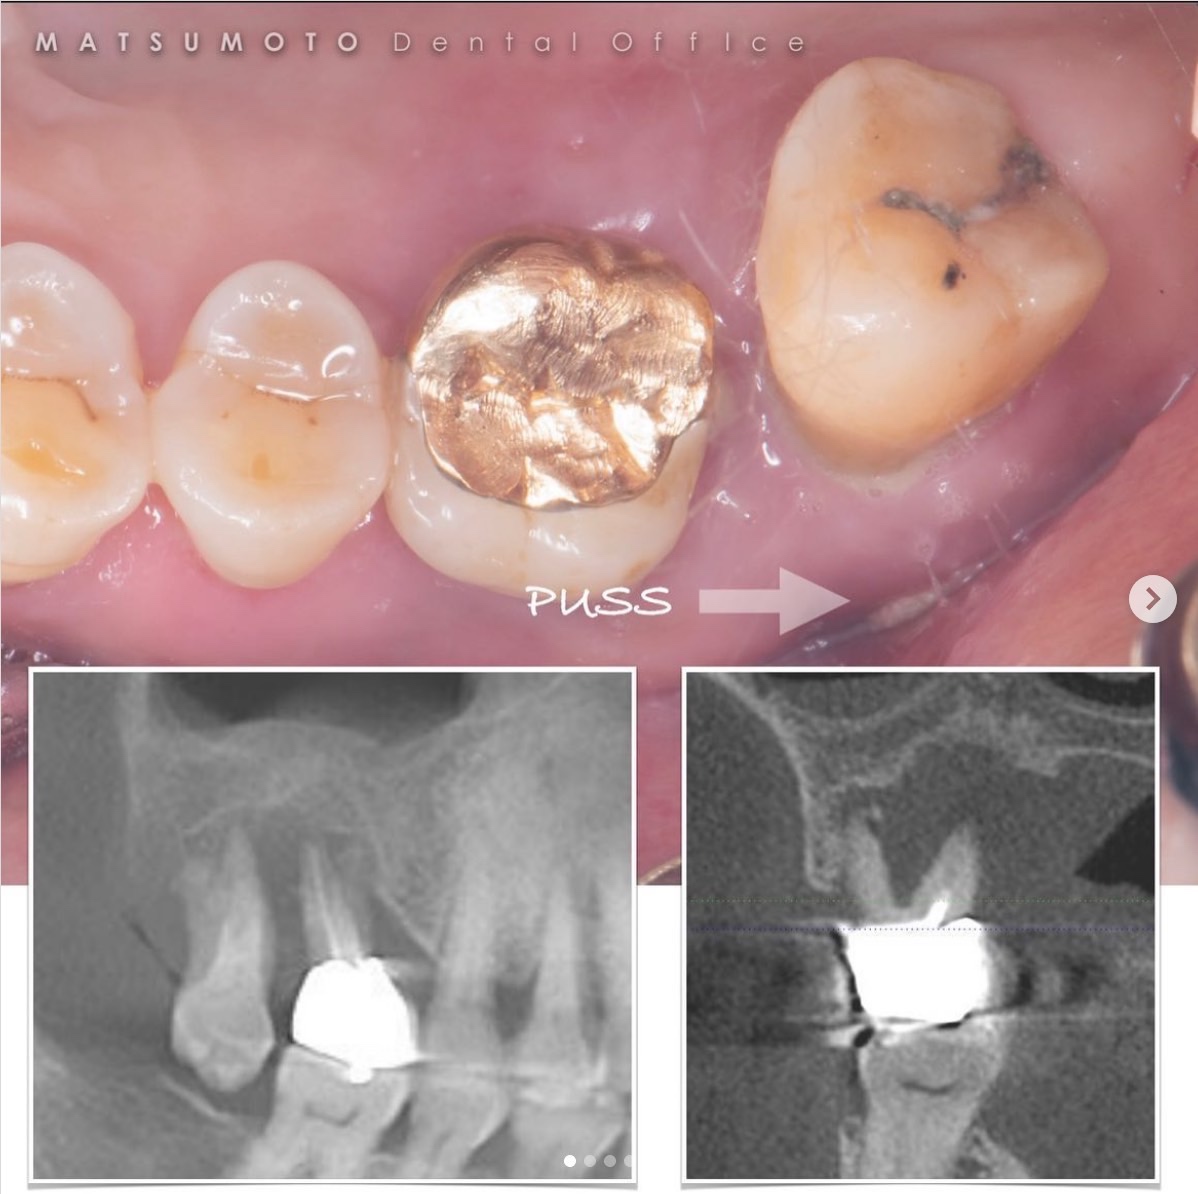

症例紹介19:インプラント治療《60代男性》

①治療名

インプラント治療

②患者情報

60代 男性

③執刀医(担当医)

松本院長

④治療内容

膿がでている歯を抜歯し、インプラント治療を行いました。

⑤治療期間

4ヶ月

⑥費用(税込)

¥1,100,000

⑦リスク

セラミックは割れたりかけることもあります。しかし、噛み合わせをはじめからしっかり合わせることによって長期的な予後を期待することができます。

インプラント治療に関することはお気軽にご相談ください😌